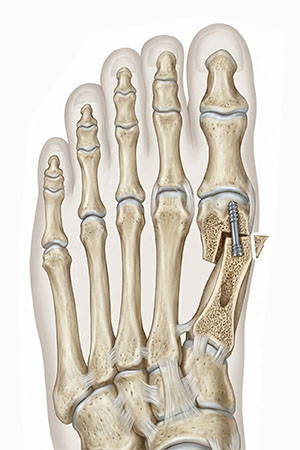

2cm 무지외반증 교정술 과정

-

01

2cm 절개로 시야를 직접 확보하여 중등도 이상의 심한 변형도 육안으로 확인하며 정교하게 수술합니다.

02

변형의 원인이 되는 주변 인대와 힘줄을 유연하게 풀어주어 수술 후 다시 휘어지는 재발 가능성을 근본적으로 차단합니다.

03

무너진 발의 구조를 바로잡기 위해 뼈를 미세하게 절골하여, 환자 개개인의 발 모양에 맞는 최적의 정렬로 만드는 절골 수술법을 선택하여 재배치합니다.

04

교정된 뼈를 특수 나사로 견고하게 고정하여 수술 직후의 완벽한 정렬을 안정적으로 유지하고 빠른 회복을 돕습니다.